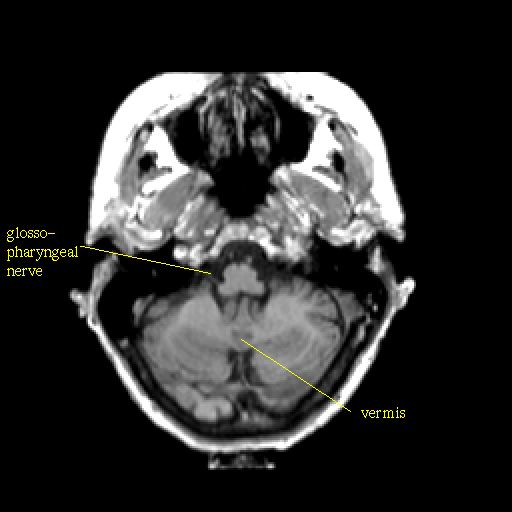

T1-weighted structural MR: Slice 11

Slice 11